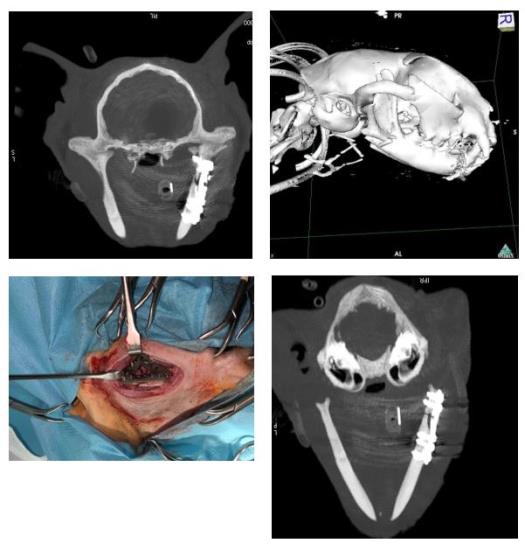

3. Collaboration on custom made Titanium plates

We’ve been collaborating with James Sage and Dan Jones from Fusion Implants and Ben Walton from ChesterGates Veterinary Specialists to design a range of 3D printed custom Titanium plates for caudal mandibular fractures in cats.

Caudal mandibular fractures in cats are challenging because the ramus is usually less than 2.5cm tall, in some areas only 1.5mm thick and access to the surgical site is limited.

We used a plate for the first case last week on a vertical fracture of the right mandibular ramus. The plate adapted to the mandible and helped to reduce the fracture very well and our patient was eating the day after surgery.